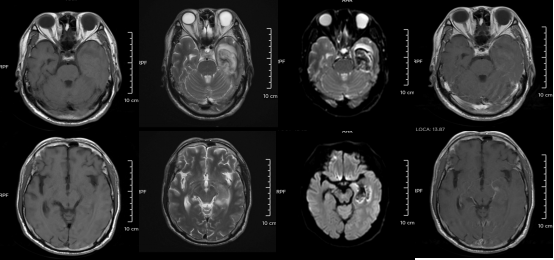

△某單純皰疹病毒性腦炎患者的醫(yī)學(xué)影像。圖源:浙江大學(xué)醫(yī)學(xué)院附屬第二醫(yī)院

但如果拖延治療,甚至?xí)l(fā)腦炎,可能出現(xiàn)癲癇、肢體偏癱、尿潴留、認(rèn)知功能障礙等嚴(yán)重后遺癥,恢復(fù)時(shí)間長(zhǎng)達(dá)3-6個(gè)月,甚至影響終身。